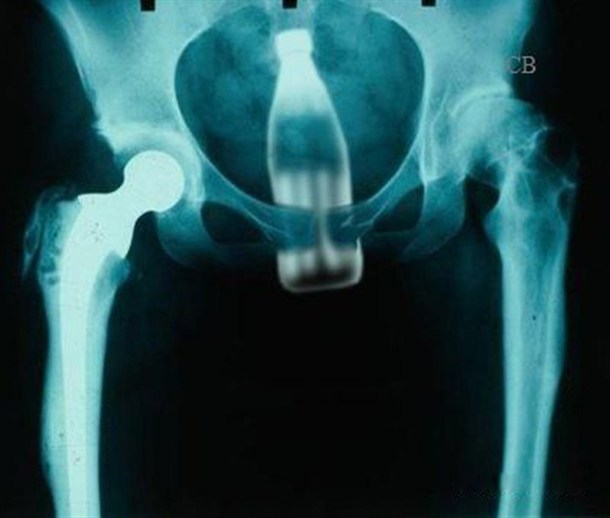

Coca Cola - Budi otvoren za nova iskustva.